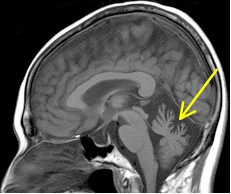

正常の小脳 脊髄小脳変性症